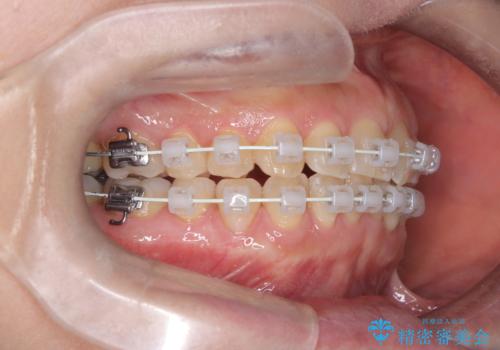

今回の矯正治療では、歯の色に近い目立たない審美ブラケットとワイヤーを使用しました。

スペース確保のために、まず奥歯全体をわずかに後方へ動かす遠心移動を実施し、前歯を並べるためのスペースを確保。さらに、安全性に配慮しながら歯の側面をわずかに削るIPRを併用し、デコボコを解消しました。

ワイヤー矯正ならではの確実な歯のコントロールにより、当初の計画通り約1年という短い期間で、前歯のガタつきが解消。見た目が美しく整っただけでなく、清掃しやすい機能的な歯並びを獲得していただけました。